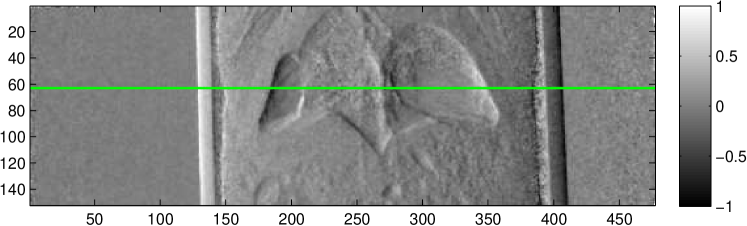

These findings are supported by the images taken from the second mouse shown in Figure 4. While in the absorption image mainly the bones and the air-filled chest cavity can be seen, the other two images allow exact distinction between the empty chest cavity and the lung tissue.

To evaluate the location of the lung tissue in the two mice computed tomographies (CT) of them were performed. This was done by rotating the object and acquiring 601 angular projections equally spaced over a full circle with the setup described in Section II.3. A reference image was taken after every 15th projection. This leads to a total of to acquire all projection images. For image reconstruction, a filtered backprojection (FBP) was applied using a ramp kernel for the absorption and the dark field data and a Hilbert kernel for the phase data after performing the phase retrieval described in Section II.2.

Exemplary for the data, one set of axial cross-sections of the lung region of the second mouse are displayed in Figure 5 (marked as horizontal lines in Figure 4). In all three CT cross-sections, the lung tissue can clearly be located in the chest of the mouse. The location found with the CT reconstruction corresponds with the location visible in the dark field projection image and the speckled area in the differential-phase image. In contrast, the exact position of the lung cannot be located with the absorption image alone.

Comparing the three images, it becomes obvious that the differential phase and the dark field image complement the absorption image and improve the identification of the shape of the lung. Especially in cases where the granularity of the lung tissue is affected, the dark field image can lead to a faster diagnosis and therefore treatment, as more information about the lung is accessible without a CT scan. It is imaginable for the identification of pulmonary oedema, where the alveoli are filled with water. This leads to a more homogeneous view of the lung and can, in combination with the higher absorption of the water visible in the absorption image, facilitate the diagnosis. Other examples for illnesses of the lung where the three different image quantities can possibly be exploited are lung cancer, pneumonia or pneumothoraxes. For the last one, example images are shown in Figure 4. In the latter, the area which is occupied by the lung is just a very small part of the chest cavity. This area can clearly be identified in the dark field projection image, while in the absorption image the contrast between space with and without lung tissue is hardly visible.

To quantify the location of lung tissue within the mouse, a CT scan of the second mouse was performed. Its results, shown in Figure 5, substantiate the above results that lung tissue is, indeed, only present in the right part of the mouse’s chest cavity in this cross-section plane. It is imaginable that an assured diagnosis can be made without a computed tomography scan, which could lead to a quickened diagnosis and a dose saving.